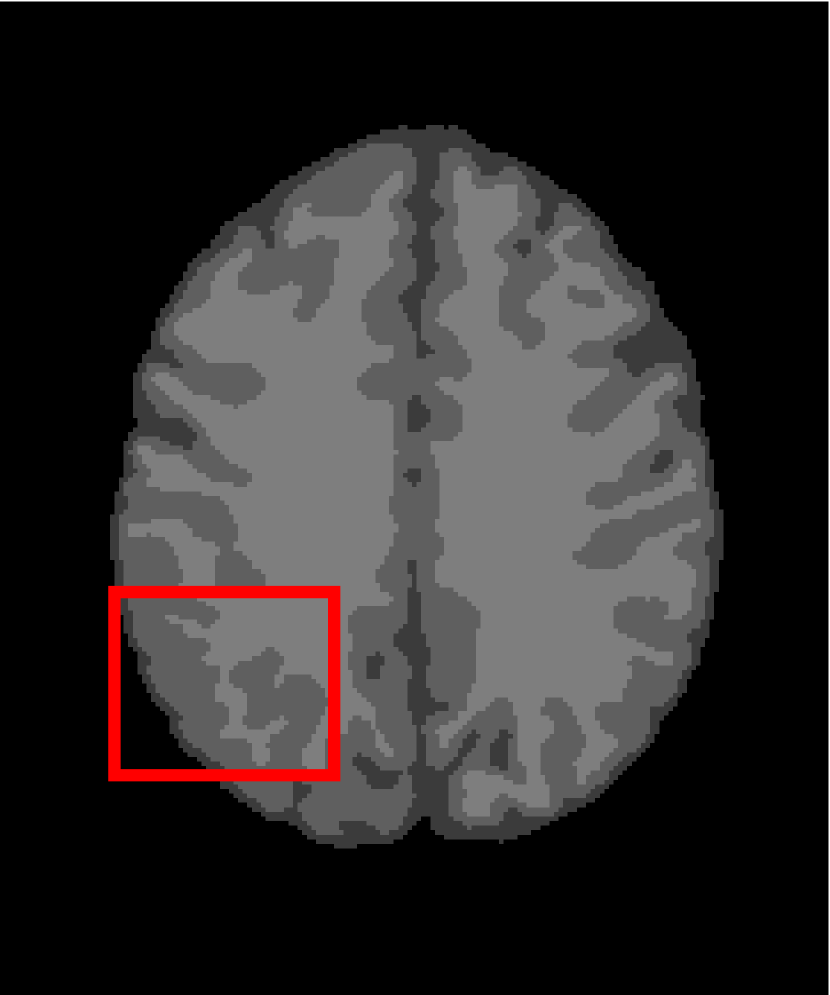

In the second experiments, we segment two medical images coming from a simulated brain database (BrianWeb): http://www.bic.mni.mcgill.ca/brainweb/. The two images are generated by T1 modality with slice thickness of 1mm resolution, 9% noise and 20% intensity non-uniformity. Here, the two images are represented two slices in the axial plane with the sequence of 100 and 110. Moreover, there are golden standard segmentations in the dataset. We set the numbers of clusters to 4. The visual comparisons are illustrated in Figs. 6 and 7.

Figure 6: Segmentation results for the first medical image. From (a) to (l): ground truth, noisy image and results of FCM_S1, FCM_S2, FGFCM, FLICM, KWFLICM, ARKFCM, FRFCM, WFCM, DSFCM_N, and LRFCM.

By focusing on the marked red square in Figs. 6 and 7, we easily find that FCM_S1, FCM_S2, FGFCM and ARKFCM are sensitive to noise. FLICM and KWFLICM are vulnerable to severe intensity inhomogeneity. FRFCM brings overly smooth results due to the use of gray level histograms. WFCM and DSFCM_N cause several contours to change. However, LRFCM acquires clear contours and suppresses noise adequately. Moreover, we find that the segmentation result of LRFCM is closer to ground truth.